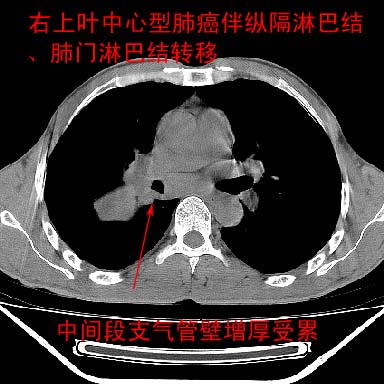

以下是引用lpc0ct在2006-11-28 16:12:00的发言:[br]大家图文并貌分析的太全面了,没有可说的,同意 [br] 右肺上叶中心型肺癌伴肺门、纵隔淋巴结转移.[br]

以下是引用dyqct在2006-11-28 16:00:00的发言:[br]右肺上叶中心型肺癌伴肺门、纵隔淋巴结转移。[br][br]